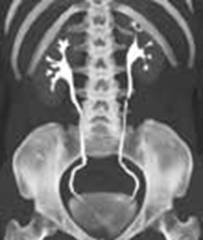

b) urograma (reconstructie longitudinala)

b)

a)

Secventele de imagini CT arata atât structurile osoase cât si tesuturile moi, inclusiv organe interne, muschi, tumori. Tonurile imaginilor (gama de nuante de la alb la negru, în functie de densitatea diferitelor structuri tisulare scanate) se cuantifica în unitati Hounsfield. Informatiile examenului (cu sau fara substanta de contrast) din multiple sectiuni transversale pot fi asamblate în imagini 3-D prin programe grafice soft dedicate.

Un examen abdominal va include imagini (felii transversale cu grosimea ≥ 5 mm) de la nivelul vârfului cupolei diafragmatice la nivelul crestei iliace, iar examenul pelvin, de la acest ultim nivel la nivelul tuberozitatilor ischiatice.